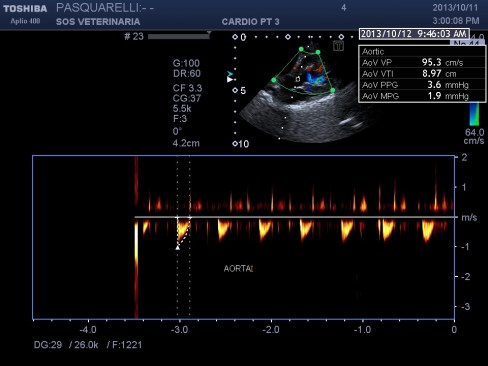

caso di cardiomiopatia ipertrofica del Maine Coone ,presentazione al pronto soccorso tipica con edema polmonare e tromboembolismo aortico completo bilaterale ,per la mia esperienza,nessun trattamento risulta essere efficace per questi soggetti, il decesso avviene nel 90%-95% dei casi e quelli che sopravvivono muoiono nelle settimane successive per le severe complicanze provocate dall’ipoperfusione ,i trattamenti trombolitici non risultano praticabili per diverse ragioni, non ultima quella economica, l’evento drammatico non e’ lo scompenso cardiaco diastolico (sul piano farmacologico gestibile) ma la trombosi aortica spesso anche polmonare .

E’ stato analizzato il fratello della stessa eta’ che e’ risultato normale.